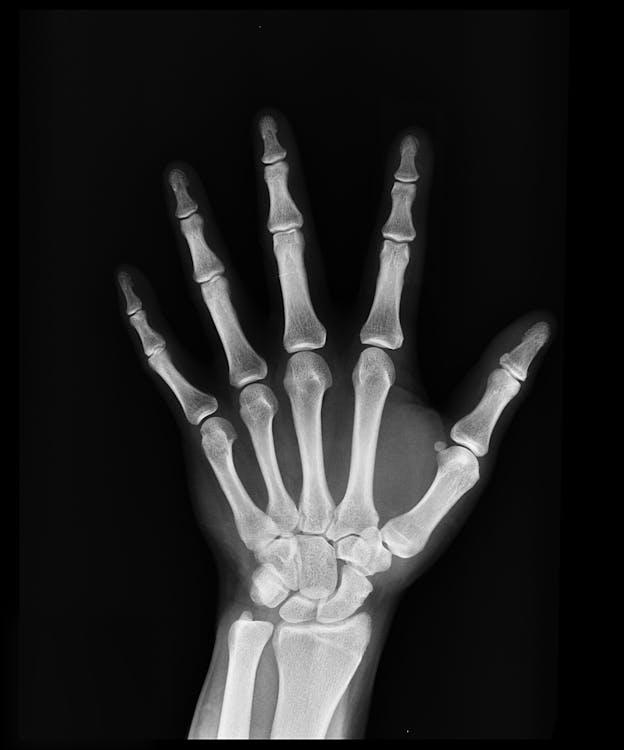

고령이 되었을 때, 골다공증은 정말 무서운 것입니다. 고령에서의 낙상사고로 인한 골절은 사망으로까지 이어지는 경우가 있기에, 조심하고 예방해야하는 상태입니다. 특히, 여성분들에게서 많이 나타나는 골다공증은 기본적으로 뼈의 밀도와 질량과 관련되어있습니다. 뼈가 약해지면서, 증상없이 진행되다가도 뼈가 부러지는 경우가 생기기 때문입니다. 한마디로, 뼈의 대사 밸런스가 무너지고, 뼈 형성보다 뼈 파괴가 웃도는 상태가 계속되고, 뼈가 부서진 상태를 의미합니다. 골다공증에 의해 뼈가 부서지면 넘어져 손과 팔꿈치를 붙인 재채기를 한 등 약간의 충격으로 골절되어 버리는 경우가 있습니다. 그렇기에 골다공증에 대한 이해와 치료는 꼭 필요합니다.   골다공증의 생리적인 이유   뼈는 '골아세포'에 의해 뼈 형성되는 동시에 ..